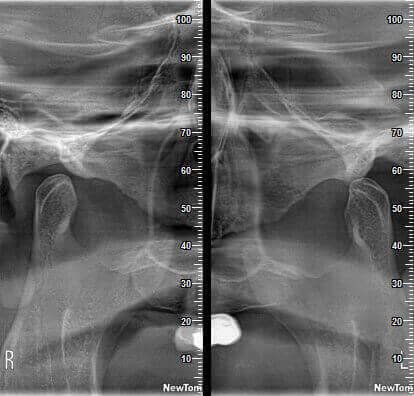

КОМПЛЕКСНЫЙ ГИБРИДНЫЙ КЛКТ ДЛЯ 2D/3D ВИЗУАЛИЗАЦИИ. ИЗОБРАЖЕНИЯ В ВЫСОКОМ РАЗРЕШЕНИИ С ЗАХВАТОМ МЕЛЬЧАЙШИХ ДЕТАЛЕЙ

GIANO HR – универсальное обновляемое устройство от NewTom для всех задач, связанных с радиографией. Благодаря полному диапазону опций 2D и 3D исследования для стоматологии оно предлагает множество особых трехмерных обследований для челюстно-лицевой хирургии, оториноларингологии и осмотра шейного отдела позвоночника. Визуализация только наивысшего качества с технологиями и опытом NewTom

NewTom GiANO HR новейшая модель была официально представлена на международном конгрессе радиологов ECR 2018 в марте в Вене. Благодаря обновленным системам механики и запатентованным механизмам работы аппарат отличается от своих сверстников Высочайшим качеством получаемых изображений, как 2D, так и 3D. Лучшее качество снимков и мы отвечаем за это! Этот аппарат заменит три аппарата! Панорамный аппарат, цефалометрическая приставка и конусно-лучевая компьютерная томография интегрированы в единую платформу. В комплекте детектор для выполнения 3D исследований с захватом области 13х16 см, Сьемный 2D CMOS детектор для выполнения панорамных исследований, и ТРГ.